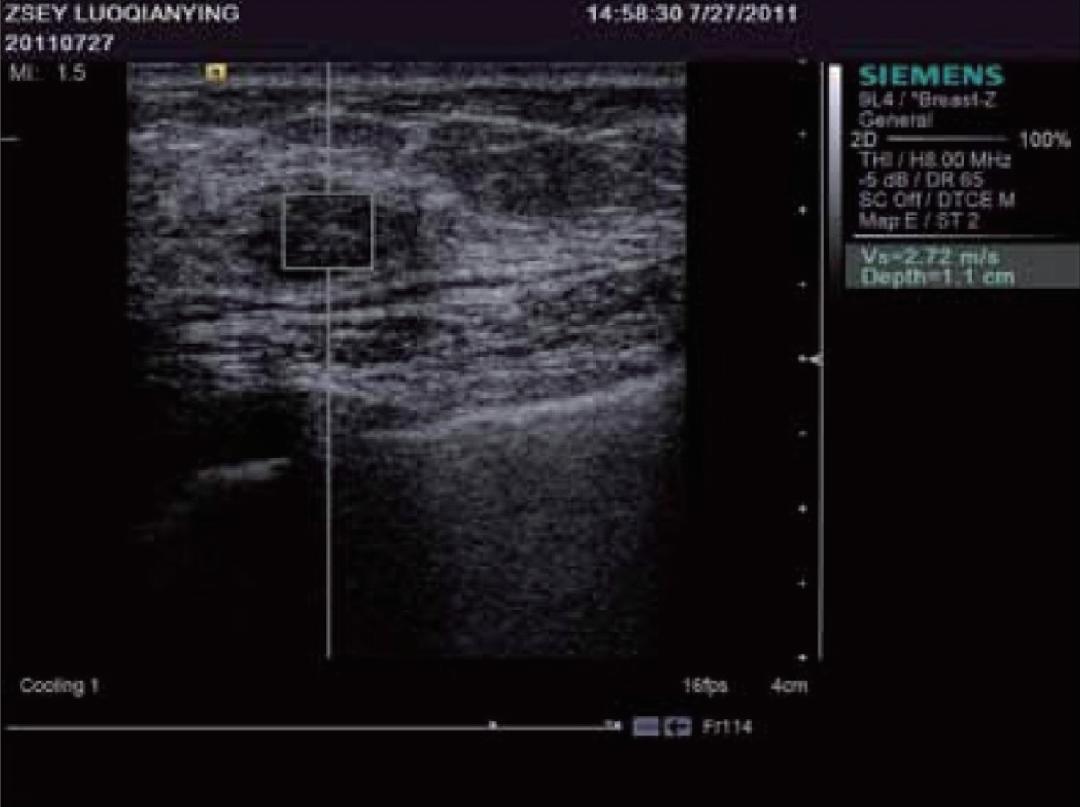

谐波运动成像最早由Maleke等人提出。 通过探头产生的超声波对组织施加周期性的声辐射力,使组织产生谐波运动。 通过获取组织被激发前后的B超图像并对其进行运动估计,可以间接反映组织的弹性状况。该方法可以准确反映深部组织的局部弹性状况,但由于需要在激发信号的同时监测组织的运动,因而采集到的B超信号容易受到激发信号的严重干扰,这是该成像方法迄今为止尚未得到完美解决的主要问题。当声辐射力作用在组织上时会激发出剪切波,剪切波弹性成像正是通过检测这一剪切波的传播来达到成像的目的,最早由美国学者Sarvazyan和Emelianov提出。他们利用高强度聚焦超声探头产生声辐射力,在人体组织中产生了明显的剪切波,并运用磁共振成像方法监测该剪切波的传播情况。由于剪切波速与人体组织的粘弹特性紧密相关,因此通过检测剪切波的传播速度等参数可以获取组织的弹性信息。图12显示了某一慢性肝病患者的肝脏弹性成像图。声辐射力脉冲成像技术最早由杜克大学的学者Nightingale等人提出,该方法通过高能聚焦超声探头在局部组织中产生短暂的高强度声辐射力,从而推动组织产生一定的应变,再通过追踪这些微小应变和剪切波的传播来判断组织的粘弹特性。研究人员发现,组织对于脉冲声辐射力的瞬态响应直接相关于局部区域的硬度大小,而通过求解亥姆霍兹方程的反问题方法可以量化组织中剪切波的波速。Nightingale等通过详细的数值仿真和体模研究证实了声辐射力脉冲成像的可行性,并得到了与传统B超图像相比更高的对比度和分辨力。如今的声辐射力脉冲成像已在临床上具备多种脏器检查的能力,图13显示了某位良性纤维瘤患者的乳腺声辐射力脉冲成像图。

图13 乳腺良性纤维瘤患者的声辐射力脉冲成像图